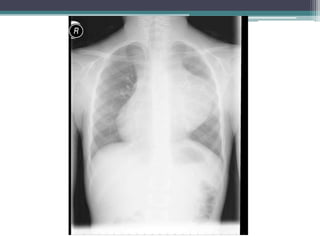

โ€ข Heart is enlarged, but hilar vessels still visible

lateral to the cardiac silhouette

โ€ข This case is pericardial effusion